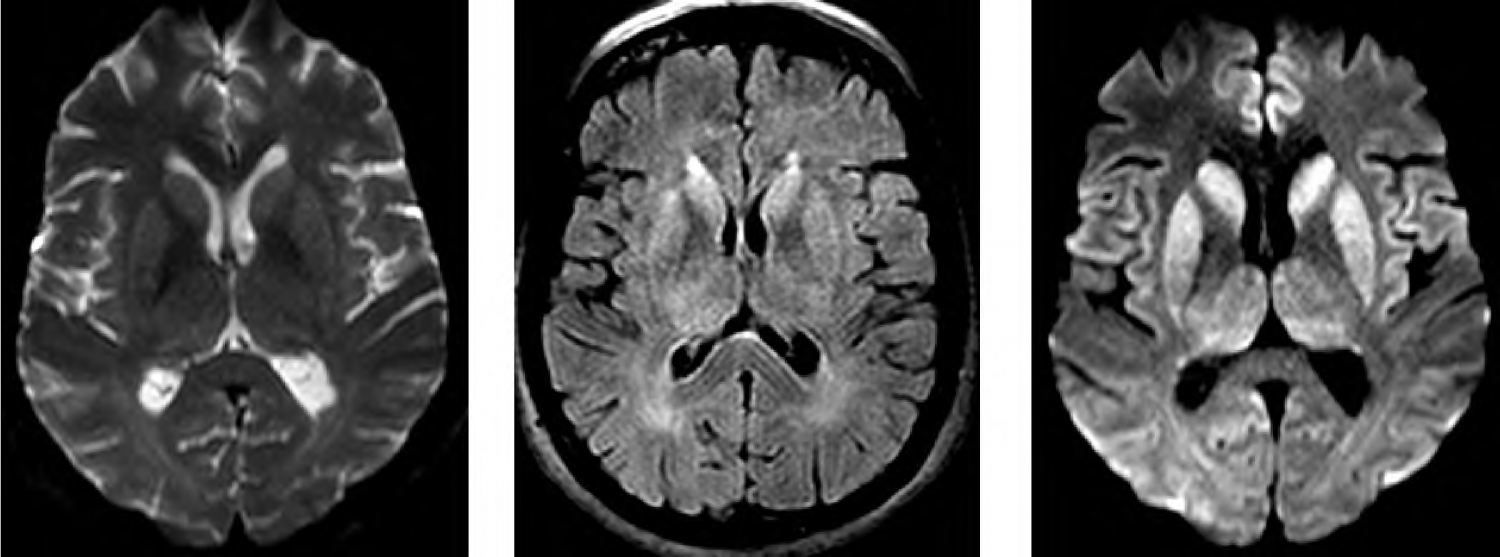

J.P, 58 anos, foi levado ao hospital com prejuízo cognitivo de início há 3 meses, com evolução progressiva, envolvendo atenção, praxia, planejamento, orientação temporoespacial, função executiva e memória. Realizado miniexame do estado mental com 12/30 pontos. Avaliação funcional evidenciou prejuízos significativos de atividades instrumentais e básicas de vida diária. A família relata que há 6 meses vem apresentando desequilíbrio e quedas frequentes. O exame neurológico revelou presença de mioclonias frente a estímulos sensoriais. Os exames de sangue gerais solicitados vieram dentro do padrão de normalidade, descartando infecções ou distúrbios hidroeletrolíticos. EEG demonstrou padrão periódico de ondas trifásicas sobre atividade de fundo atenuada. Realizou exame de ressonância de crânio (T2, FLAIR e DWI) que mostrou as seguintes imagens: